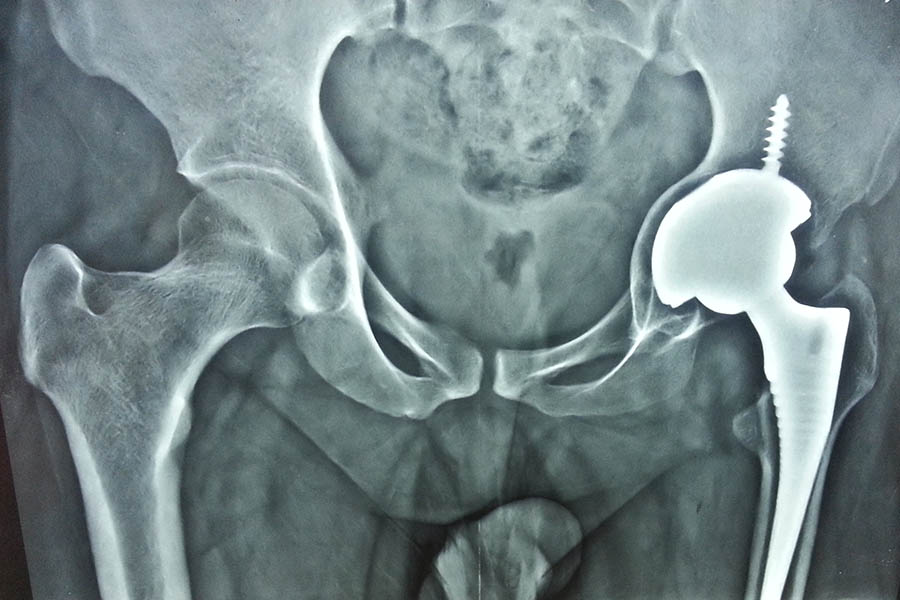

Total Hip Replacement

Case 2